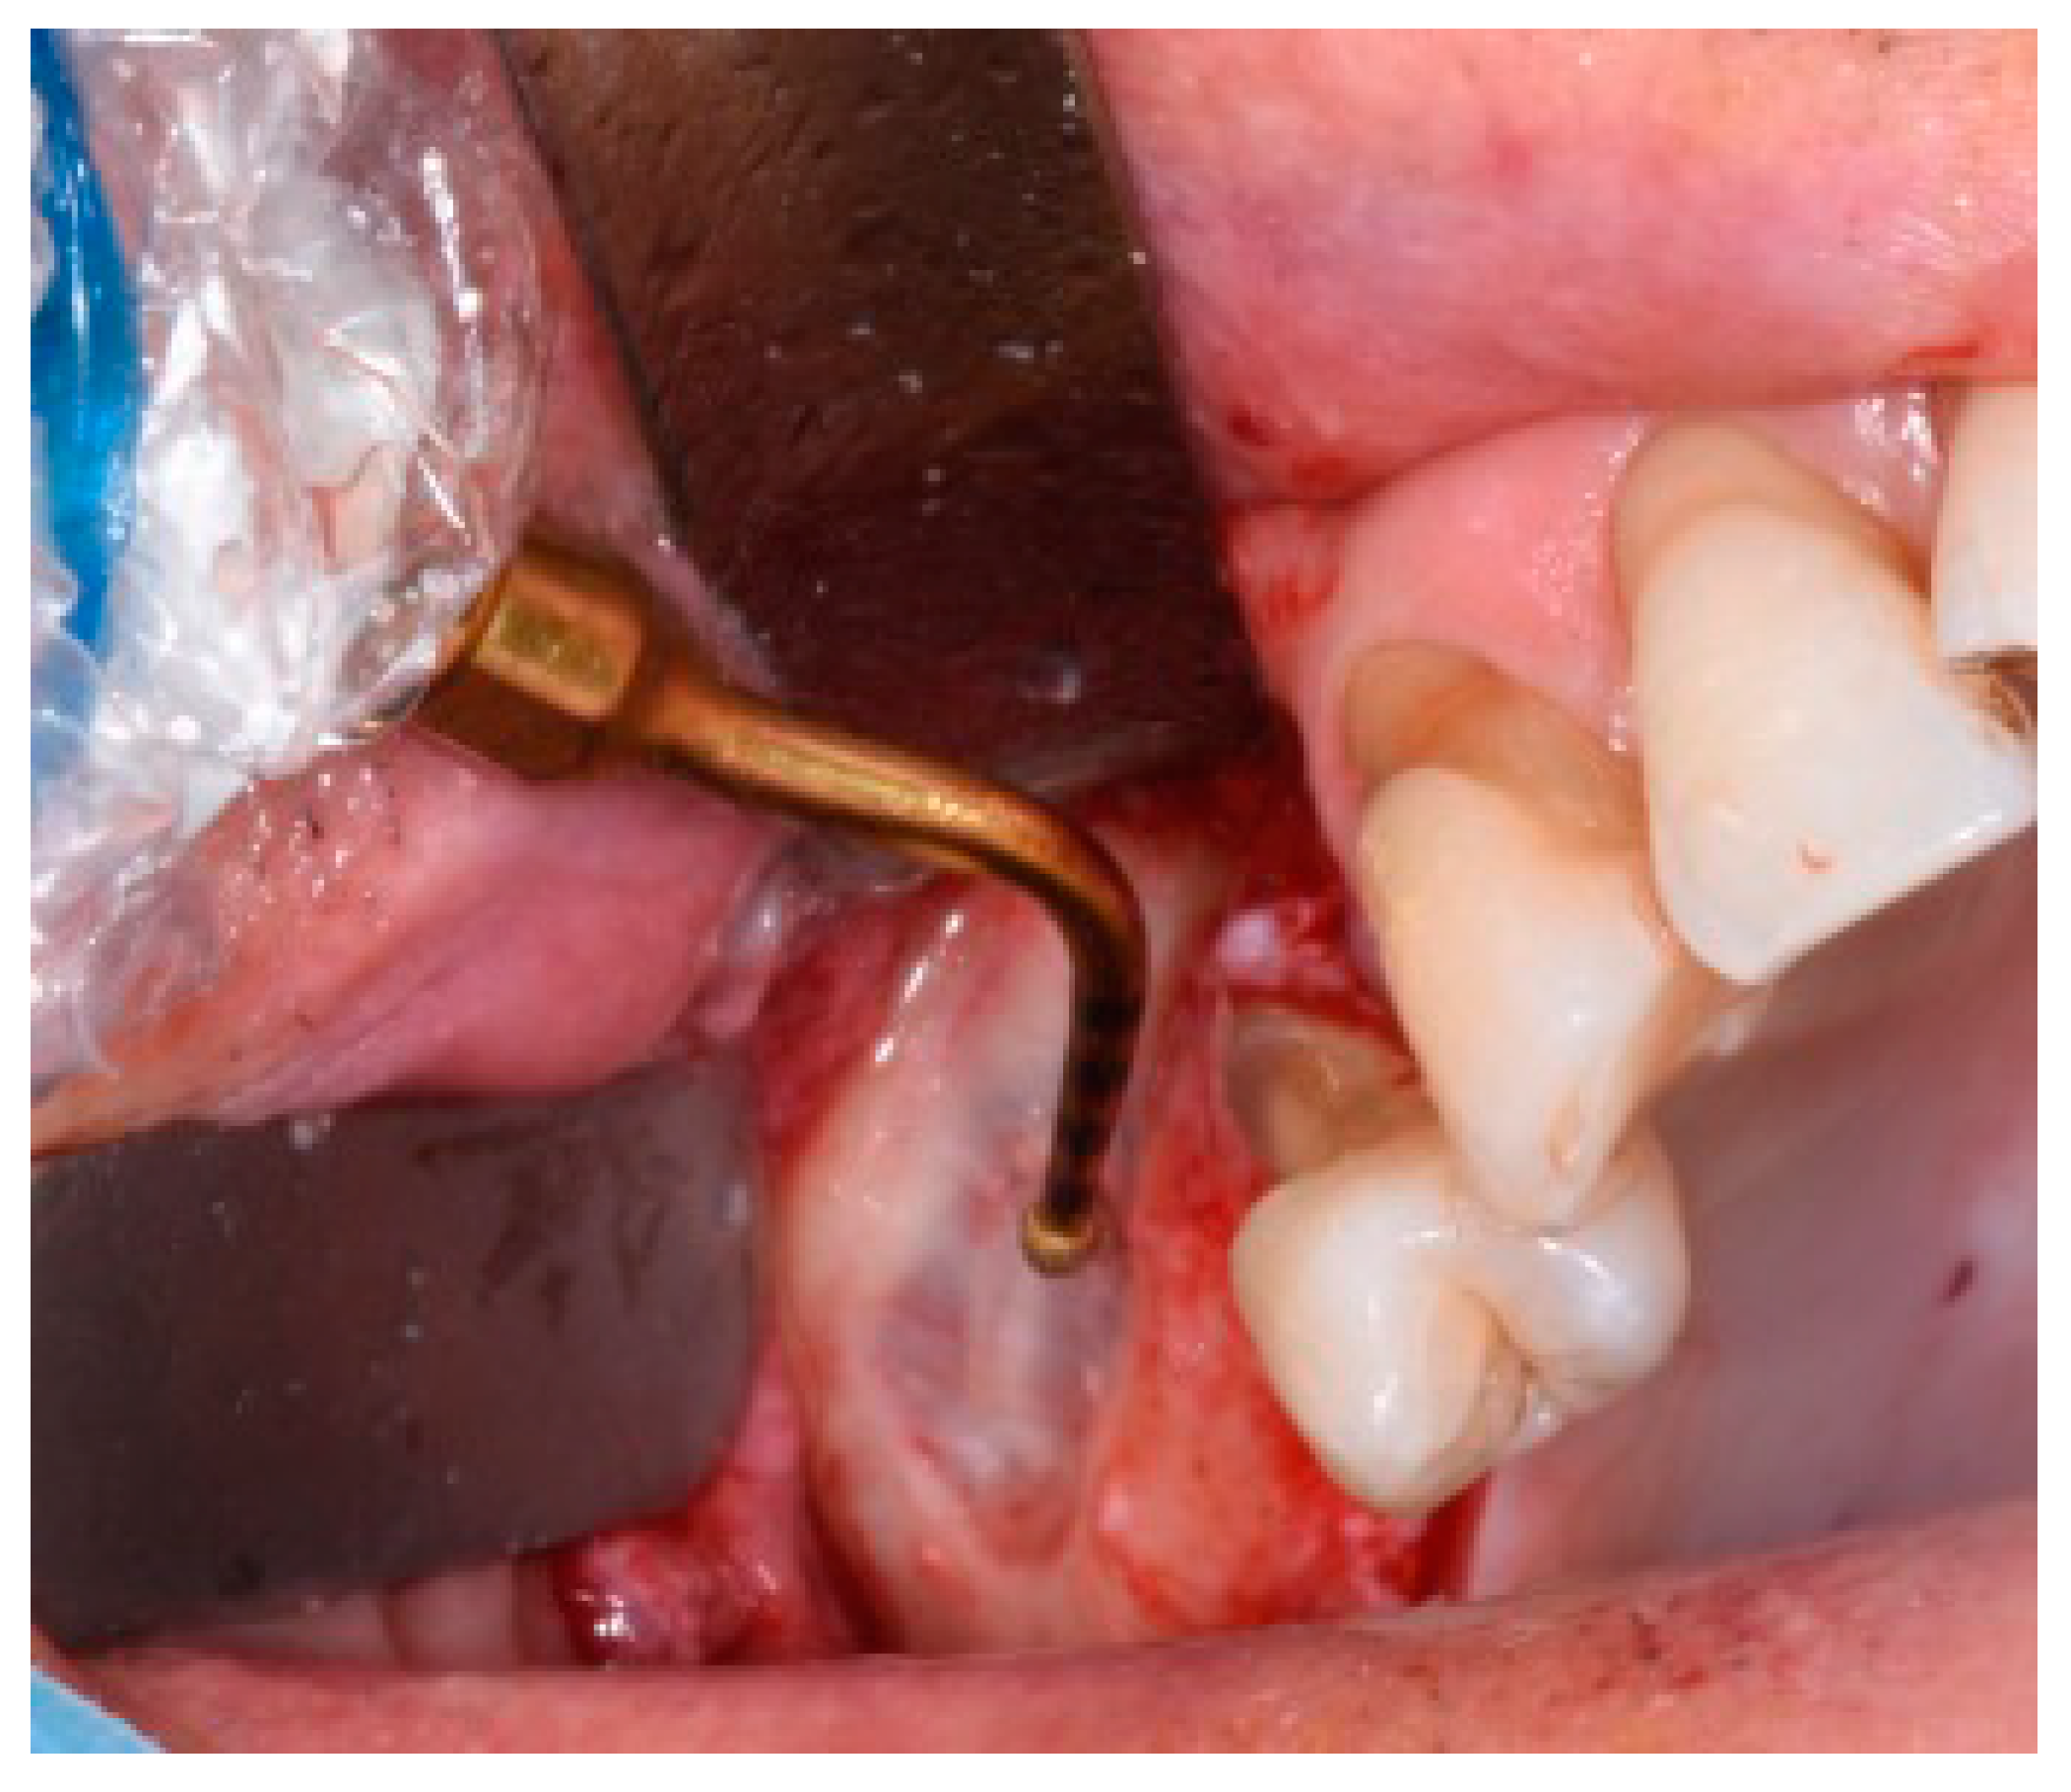

Figure 4.

Detail of the sinus filling and the bone tacks.

Once the flap was raised, a bone window was opened, using the Mectron Piezosurgery System (Genova, Italy), to gain access to the maxillary sinus, as reported in Figure 1. The bony wall was reduced using an osteotomy tip until the Schneiderian membrane became evident in the fully shaved area, and bone window dimensions were approximated. The sinus membrane was lifted starting from the inferior border of the osteotomy site and completely and carefully dissected in the posterior, lateral, median, and mesial walls of the sinus. All surgical procedures were performed with great accuracy to avoid damage and perforation of the membrane. Once the sinus was elevated, the space was filled with deproteinized bovine bone (1 gr, particles 1–2 mm, Bio-oss, Geistlich Pharma Italy, Thiene, Italy) with manual filling, and the bony window was covered on the buccal surface with a resorbable collagen membrane 13 × 25 mm (Bio-Gide Geistlich Pharma Italy, Thiene, Italy), as reported in Figure 2. At this point, exclusively in the study group, two bone tacks were placed on the mesial and on the distal central surface of the membrane (Kalos, Nike, Orbetello, Italy), as reported in Figure 3 and Figure 4. Mattress sutures were placed on the crestal incision, and single stitches were placed in the release incisions (vicryl, ethicon, Johnson & Johnson, New York, NY, USA).